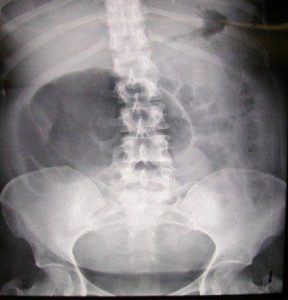

მეცნიერების განცხადებით, ის ფაქტი, რომ ქალები ფიზიოლოგიურ მშობიარობას სულ უფრო ხშირად საკეისრო კვეთას ამჯობინებენ, ადამიანის ევოლუციაზე აისახება. კერძოდ, თუ ადრე ვიწრომენჯიანი ქალები დიდ ბავშვებს ვერ აჩენდნენ და მშობიარობის დროს ბავშვი ან დედაც და ბავშვიც იღუპებოდნენ, ახლა ეს შესაძლებელი გახდა. შესაბამისად, ასეთი ქალები გენებს მომავალ თაობებს გადასცემენ.

ანუ მეცნიერების კვლევის მიხედვით, სახეზეა ვიწრომენჯიანი ქალების რაოდენობის ზრდა და ადამიანის საშუალო წონის მატებაც.